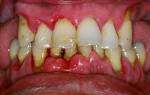

Фото 2. Слева – фото до процедуры по удалению зуба, справа видны последствия – изменение прикуса.

Фото 3. На фото видны изменения, к которым привели зубы мудрости, при этом остальные начали сдвигаться, торчать в разные стороны.